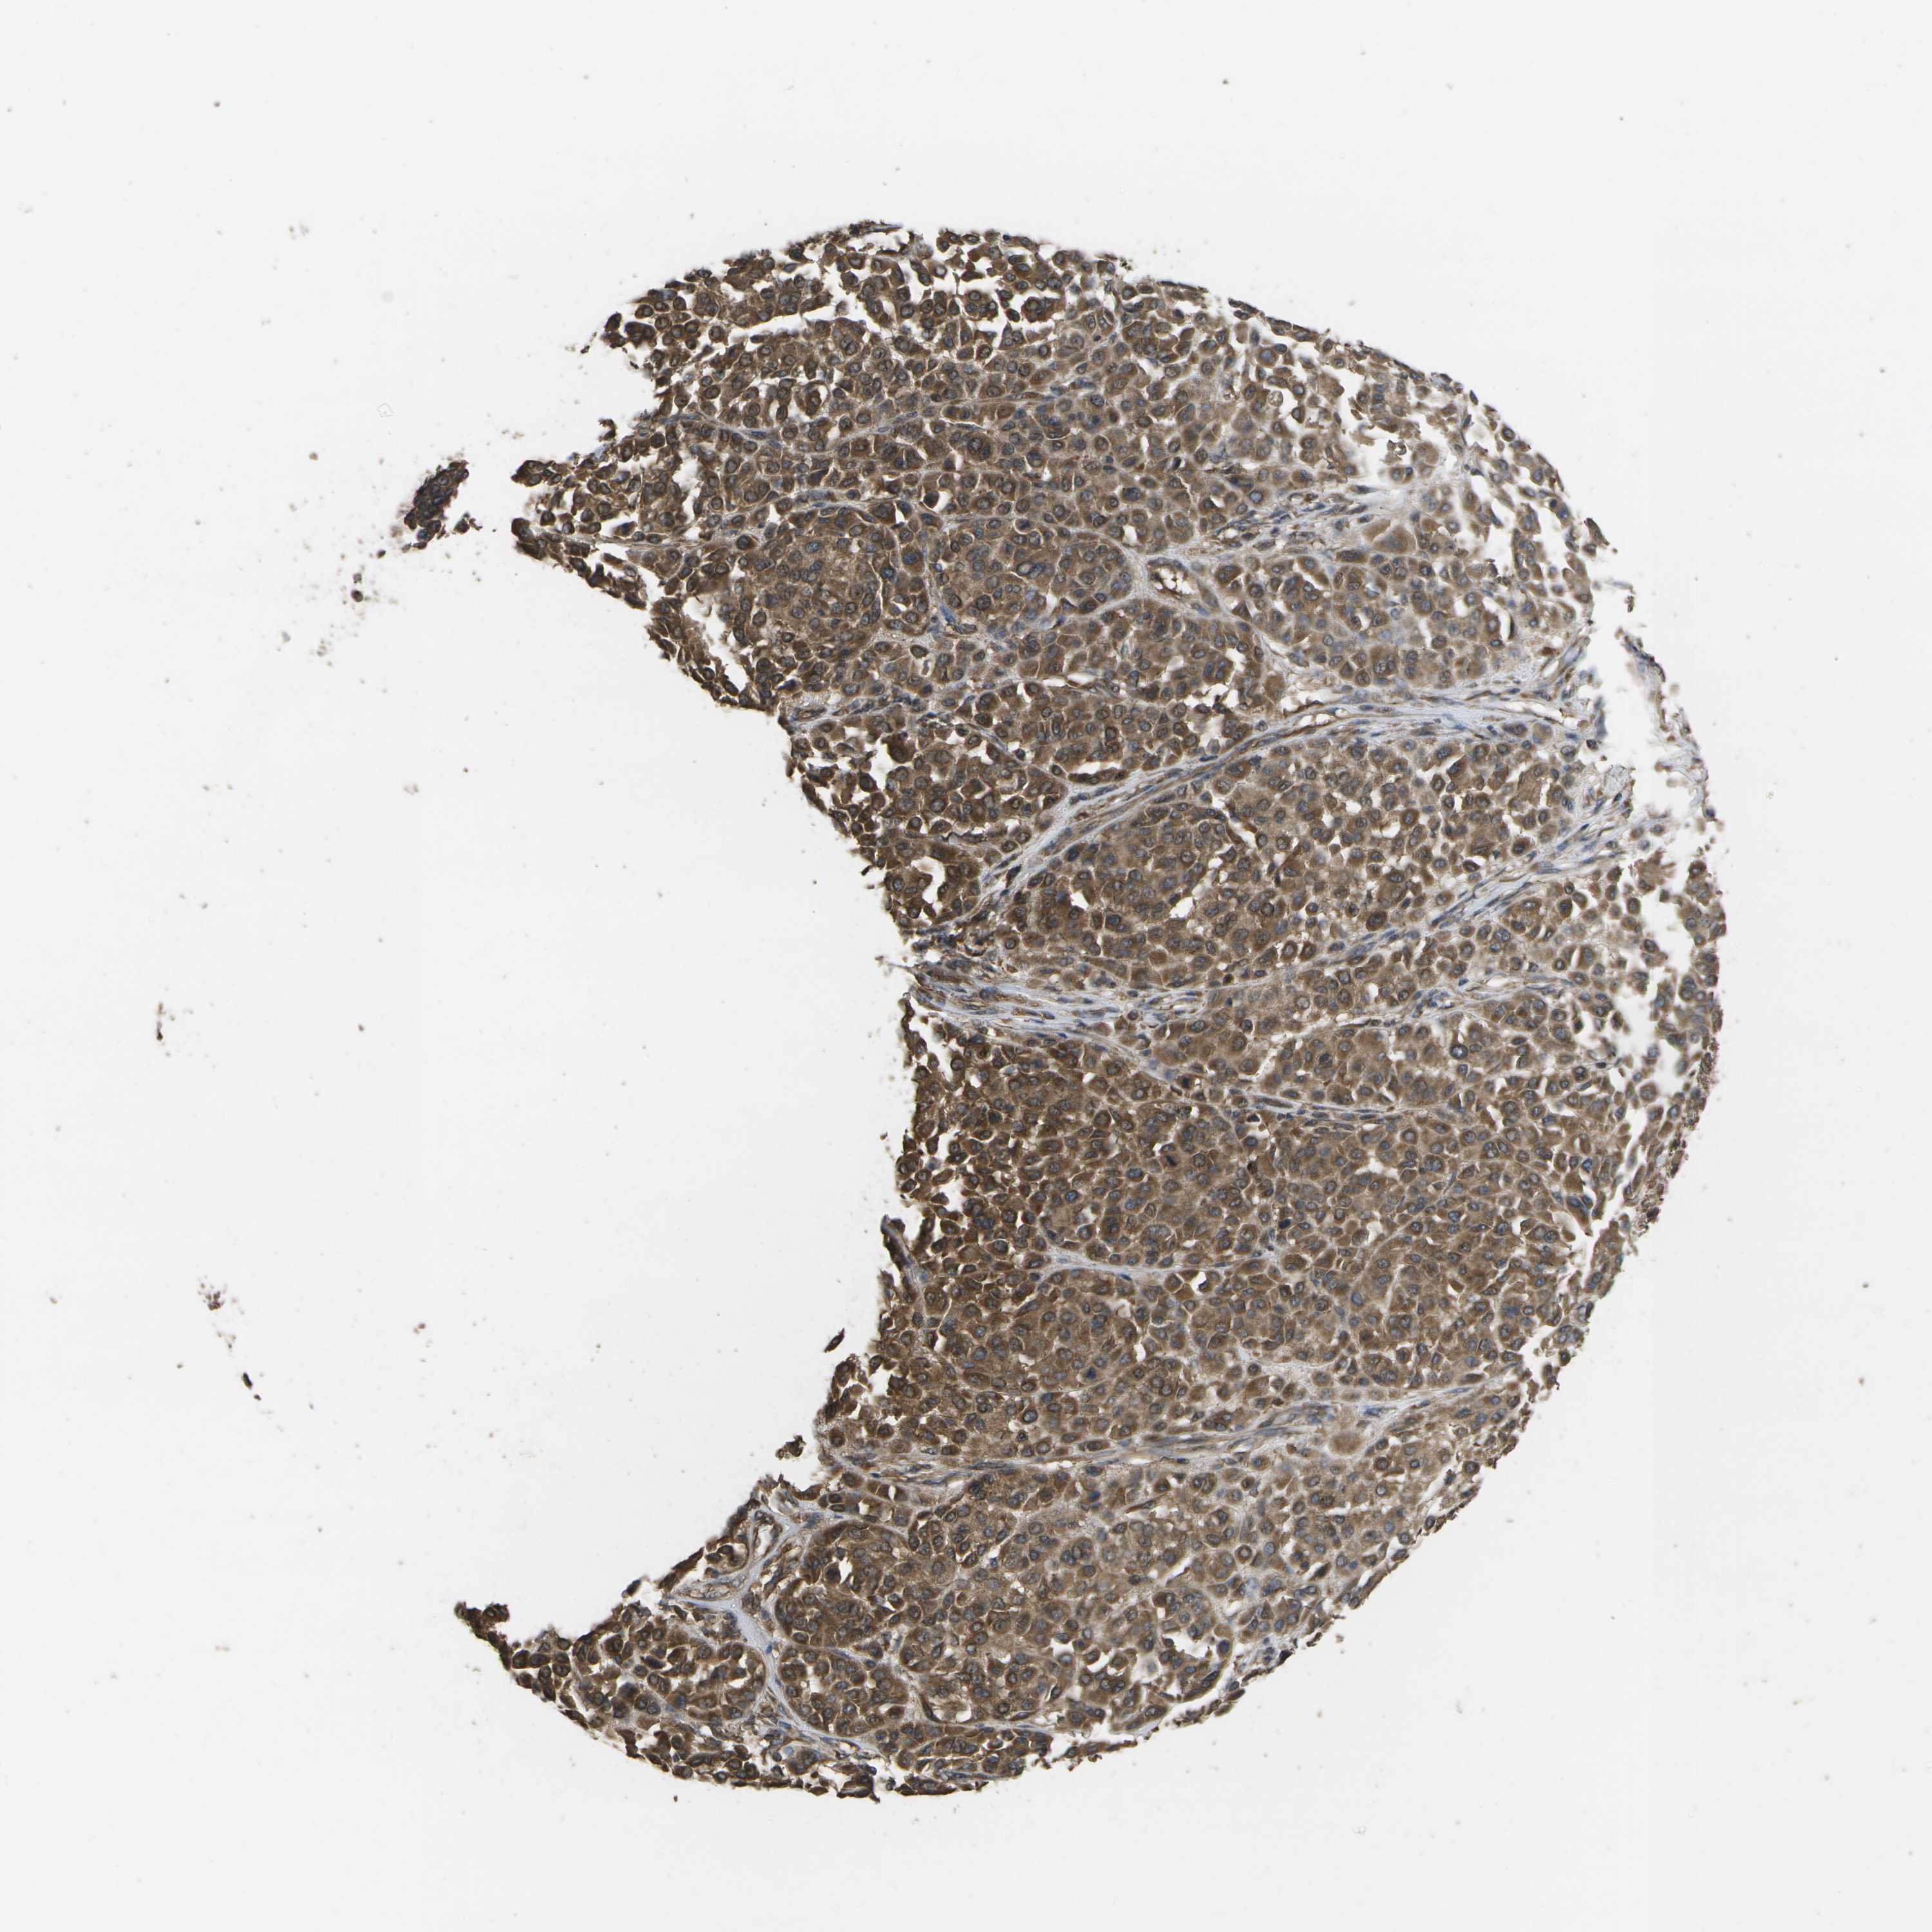

MELANOMA - Protein expressioni

A mouse-over function shows sample information and annotation data. Click on an image to view it in a full screen mode. Samples can be filtered based on level of antibody staining by selecting one or several of the following categories: high, medium, low and not detected. The assay and annotation is described here.

Note that samples used for immunohistochemistry by the Human Protein Atlas do not correspond to samples in the TCGA dataset.

Antibody stainingi

Antibody staining in the annotated cell types in the current human tissue is reported as not detected, low, medium, or high, based on conventional immunohistochemistry profiling in selected tissues. This score is based on the combination of the staining intensity and fraction of stained cells.

Each image is clickable and will lead to virtual microscopy that enables deeper exploration of all samples and also displays staining intensity scores, fraction scores and subcellular localization as well as patient and tissue information for each sample.

Antibody CAB017714

Staining

High

Medium

Low

Not detected

Intensity

Strong

Moderate

Weak

Negative

Quantity

>75%

75%-25%

<25%

None

Location

Nuclear

Cytoplasmic/membranous

Cytoplasmic/membranous,nuclear

Malignant melanoma, NOS

Malignant melanoma, Metastatic site